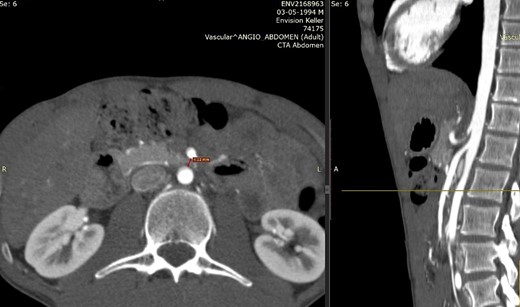

We present the case of a 21-year-old male patient, with a history of laparoscopic cholecystectomy and 3 cryoablations for Barret’s esophagus with grade III dysplasia, who presented with persistent postprandial vomiting that had caused weight loss of 11 kg in the last 2 years without apparent cause, associated with gastroesophageal reflux that has worsened over time, occasional stabbing abdominal pain in the epigastrium, painful constipation, bloody stools and steatorrhea, managed clinically and symptomatologically without improvement in the condition. On evaluation, the patient was thin, with a BMI of 17.31 kg/m2, and in paraclinics, in endoscopy (Figs 1 and 2), Barret’s esophagus and hiatal hernia; In tomography (Figs 3 and 4), an aortomesenteric angle of 17.5°, with aortomesenteric distance of 4 mm.

Computed tomography. Aortomesenteric distance of 4 mm. Wilkie’s syndrome.

Given the diagnosis of gastroesophageal reflux disease (GERD) with esophagitis + SAMS (Wilkie syndrome), surgical resolution was decided (Fig. 5), showing trans surgical findings of open diaphragmatic pillars, normal stomach, absence of duodenal distension, and presence of duodenal compression due to AMS. Finally, robotic-assisted laparoscopic anterior and posterior hyatoplasty + Nissen fundoplication + duodenojejunostomy were performed, without complications.